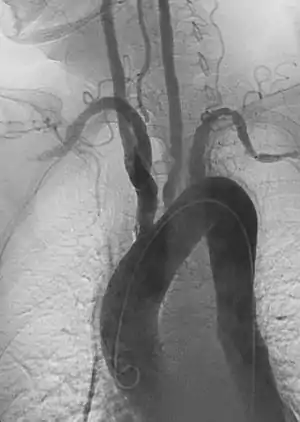

- Angiography: Sometimes referred to as traditional angiography, catheter angiography or digital subtraction angiography (DSA.) A small needle is inserted into a blood vessel, then exchanged for a catheter over a wire. The catheter is directed at the vessel to be studied, and contrast is directly injected to evaluate the lumen under video X-ray. This is an older technique than modern CT Angiography or MR Angiography, but provides unique advantages. With a catheter in place, provocative maneuvers can be performed such as breath holds or instillation of vasodilators, to evaluate a patient's blood flow dynamically. This can reproduce symptoms and identify functional abnormalities in a vessel that a static CT or MR imaging cannot.[79][80] Angiography provides the basis for all endovascular therapy.

- Aortic Aneurysms include thoracic, abdominal or thoracoabdominal. Treatment strategies are customized depending on the location, size, rate of growth and extent of the aneurysm as well as the medical comorbidities of the patient. For example, an intact, small but slowly growing aneurysm may be safely monitored with serial imaging for months or years before elective repair is considered. Elective endovascular aortic grafting is now routinely attempted when possible. Endovascular Aortic Repair (EVAR) refers to treatment of an abdominal aortic aneurysm, while Thoracic Endovascular Aortic Repair (TEVAR) is performed on the thoracic aorta. A ruptured aneurysm may be taken emergently for open, endovascular or combination repair.

A variety of endovascular grafts are available, and each has advantages and disadvantages depending on the characteristics of the aneurysm and patient (RFS EVAR/TEVAR webinar: https://www.youtube.com/watch?v=rjRClHP1dEc)